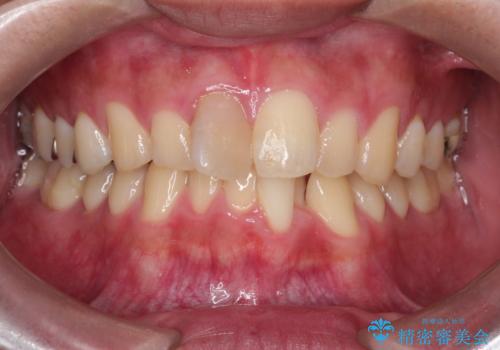

- 「上の前歯の捻じれと下の前歯のでこぼこを治したい」を主訴に来院された患者様です。

矯正検査の結果、非抜歯で矯正可能だったためインビザラインで治療を行いました。

アーチの拡大とIPRで叢生を改善いました。

11ヵ月で矯正を終える事ができ患者様も大変ご満足されていました。